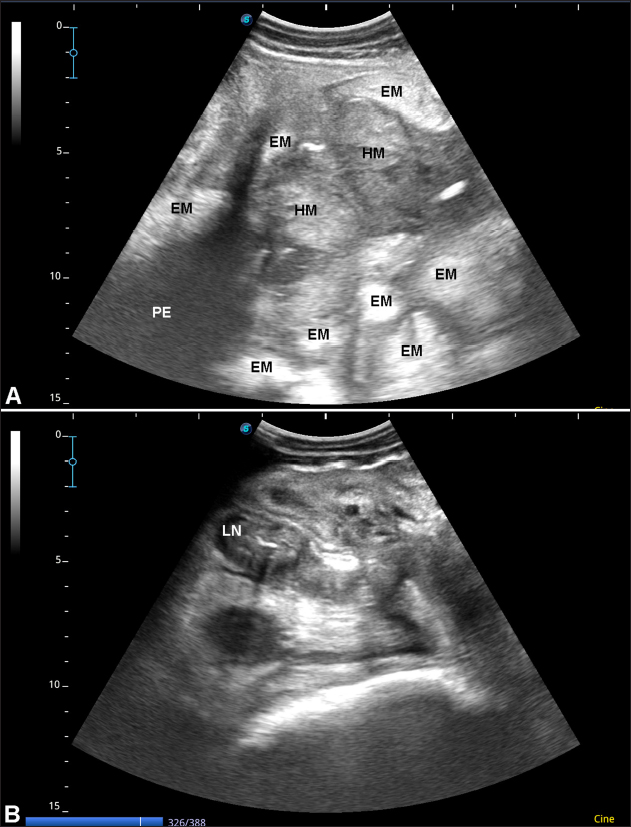

On the right side of the abdomen, transabdominal ultrasonography revealed multiple echogenic masses located within the intestinal loops; some of the masses are hypoechogenic. Other findings included hyperechogenic peritoneal effusion and enlarged calcified mesenteric lymph nodes (Fig. 2).

Fig. 2. Ultrasonographic findings in a 7-year-old female dromedary camel with abdominal fat necrosis. Sonography of the right side of the abdomen showed multiple echogenic masses (EM) located within the intestinal loops; some of the masses are hypoechogenic (HM). Hyperechogenic peritoneal effusion (PE) was also imaged (A). Enlarged calcified mesenteric lymph nodes (LN) with distal acoustic shadowing was additional finding (B).

Ultrasonographically, cattle with abdominal fat necrosis shows heterogenous hyperechoic masses, echogenic omentum with localized, non-capsulated masses floating in echogenic peritoneal effusions. Kidneys were imaged surrounded by hyperechoic rims and intestines were surrounded by hyperechogenic capsule (Tharwat and Buczinski, 2012). In dromedary camels, ultrasonog../sample/Final-Updated/14(7)/New%20folder/100-1700834438_2R.pdfraphy has been proved effective for verification of different disorders (Tharwat, 2020a,b,c; Tharwat and El-Tookhy, 2021; Tharwat et al., 2023; Tharwat, 2024; Tharwat et al., 2024a,b). In the present case, transabdominal sonography revealed multiple echogenic masses located within the intestinal loops; some of the masses are hypoechogenic. A Hyperechogenic peritoneal effusion and enlarged mesenteric lymph nodes were also detected. It was also proved that ultrasound is valuable in dromedary camels for assistance in antemortem diagnosis of abdominal masses (Sadan et al., 2024).